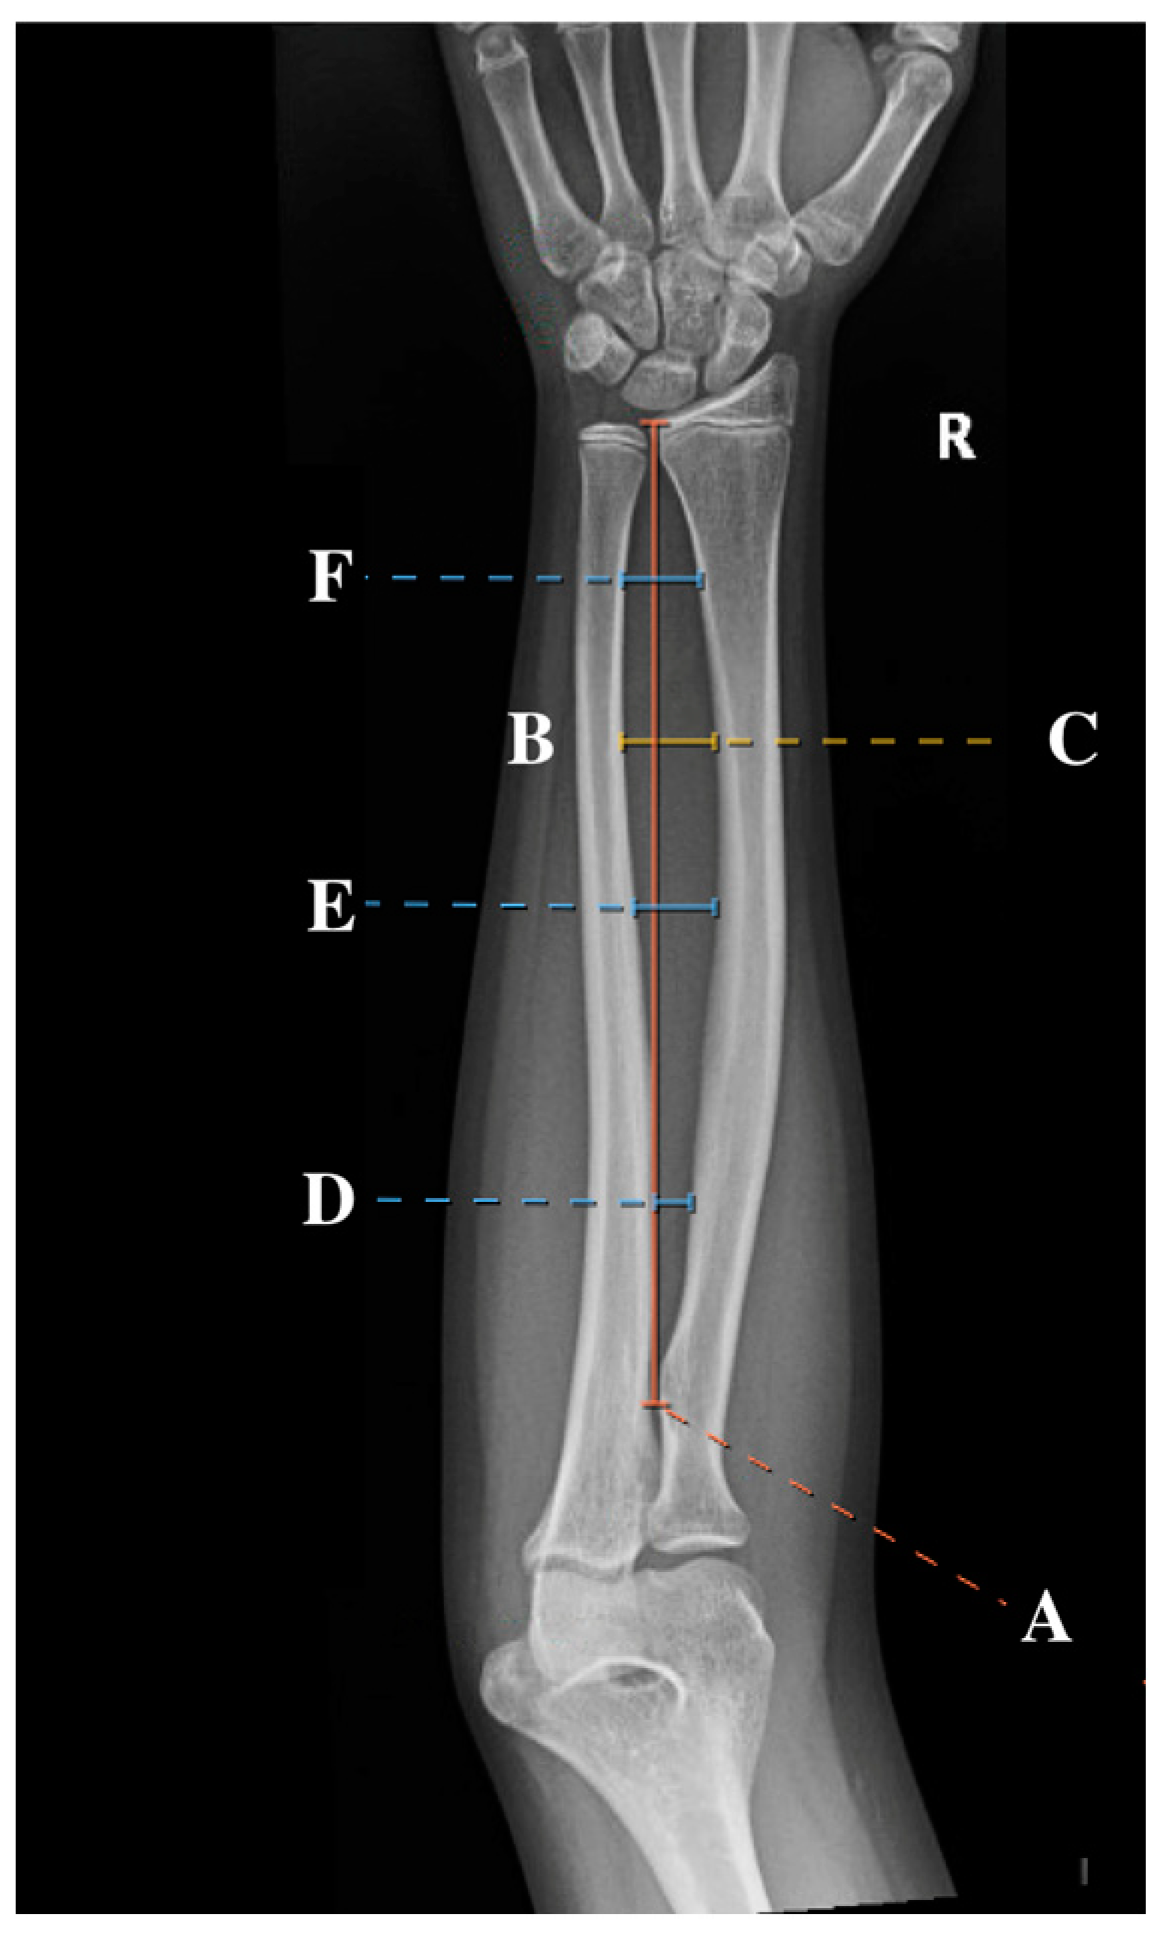

Standard AP radiographs were obtained from the IMPAX imaging system. Subsequently, the IMPAX imaging system measuring tool was used to measure the location of the maximum radial bow, as initially described by Schemitsch and Richards [4,7]. Measurements also included the total radial length (measured as the distance between the biceps tuberosity and the distal radial ulnar joint (DRUJ)), location of maximal radial bow (measured as both the distance from biceps tuberosity to the apex of the radial bow and the percentage of total radial length), and depth at maximal radial bow (measured both as the distance from the cortex of the radius at the maximum bow to the cortex of the ulna and as the percentage of total radial length). These measurements, represented as a percentage of the total radial length, were utilized to normalize the values to allow for comparison across age groups, similar to the methodology employed in previous studies [2,4,10]. In addition to these previously described measurements, the location of the proximal, middle, and distal third of the radial bow was recorded. A sample of the measurements can be found in Figure 1. All measurements were performed by four observers (SK, RL, CM, and AF) to improve generalizability to other surgeons.

Figure 1.

An AP radiographic view of the forearm of a 12-year-old female with the six measurements included in this study: total radial length (A), location of the radial bow (B), maximum radial bow (C), and proximal (D), middle (E), and distal (F) radial bow.